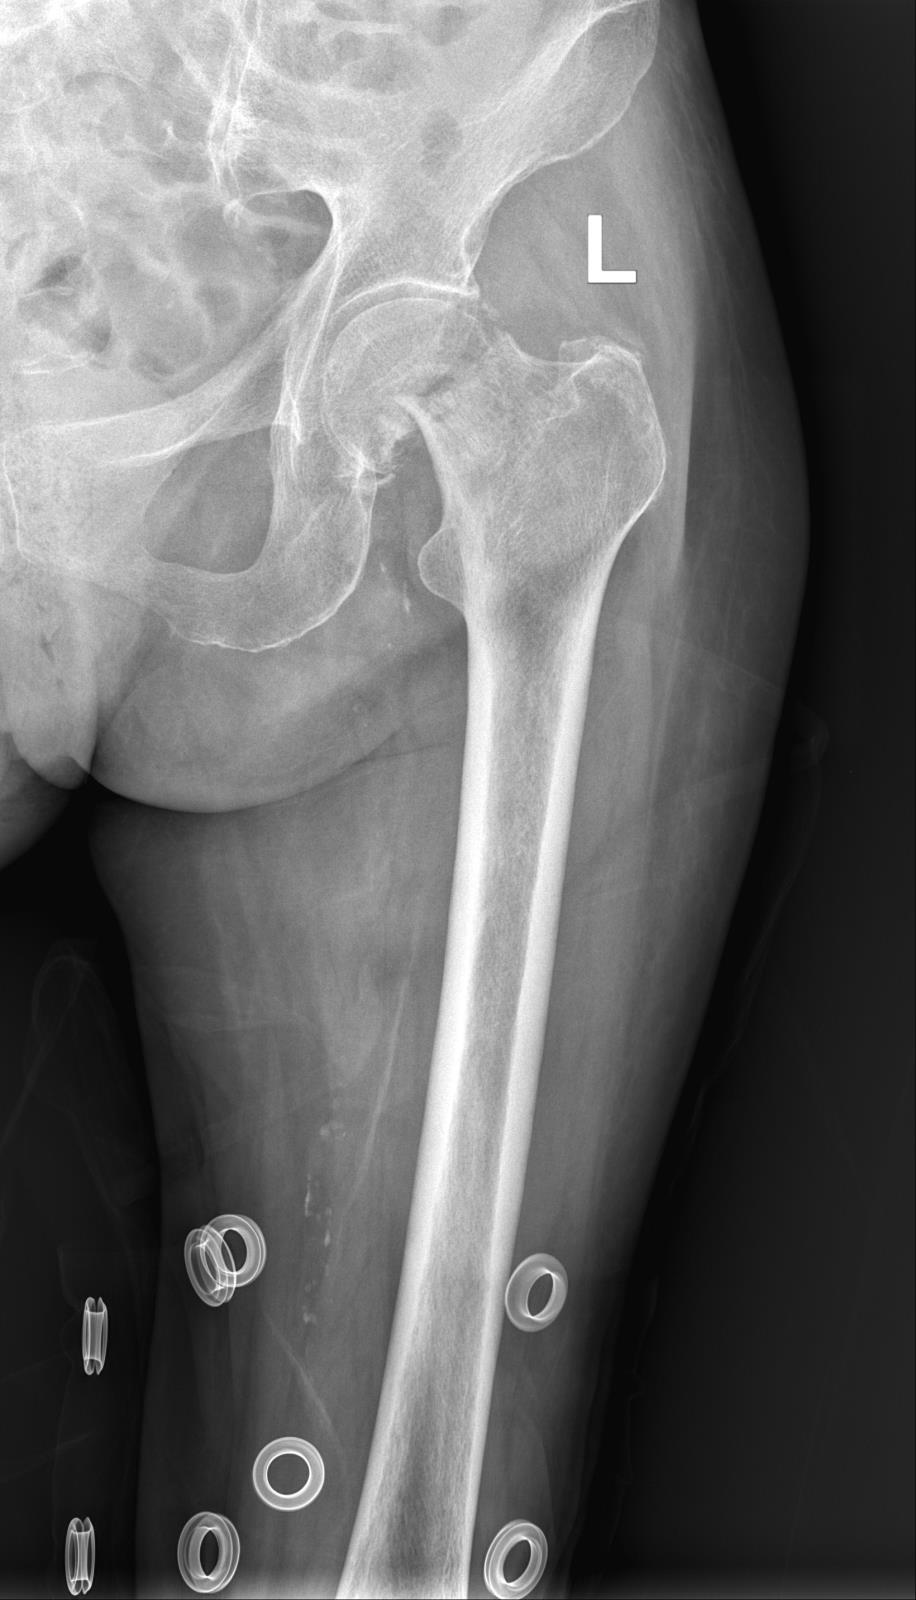

近日,一位九十多岁高龄老婆婆因不慎摔倒髋部骨折,患者年龄偏高,身体基础条件较差,面对号称“人生最后一次骨折”的髋部骨折,如果只是保守治疗,由于老年人髋部骨折的特殊性,可能还未待到3个月左右骨折愈合好后,就会发生下肢静脉血栓、压力性损伤、泌尿系统感染等严重并发症,危及老人的健康甚至是生命安全。在这种疫情背景下的特殊时期,能够进行手术吗?

术前DR 术后DR

在严格执行疫情防控要求下,急诊科将患者转运至综合缓冲病房进行治疗,并积极完善相关术前检查,实行三天三检(核酸检测),均为阴性后当天立即转入骨科病房,大外科党委书记、大外科主任、骨科主任肖聪带领科室医疗团队结合患者的各项检查指标结果,进行缜密的病例讨论,与家属商量决定为患者行微创全髋关节置换术。

术前,骨科积极联系相关科室,进行了充分的术前准备,麻醉科指派丰富经验的麻醉师时刻关注患者麻醉期间各项指症数值,全程保驾护航。经过1小时的手术,微创全髋关节置换术成功完成,麻醉完全苏醒后即刻下地行走进行功能锻炼,极大预防了老年患者因卧床导致致命的深静脉血栓、肺部感染、泌尿系统感染等并发症,在专业康复理疗师的指导下进行功能锻炼,目前患者恢复良好,择日即可办理出院。

目前我院骨科已开展微创全髋关节置换日间手术,当天手术麻醉苏醒后立即走出手术室,无痛感,术中出血少,不安置引流管、导尿管、不拆线,手术切口小(仅9cm),当天就可以办理出院,快速回归家庭、社会,极大减轻了患者的经济负担。